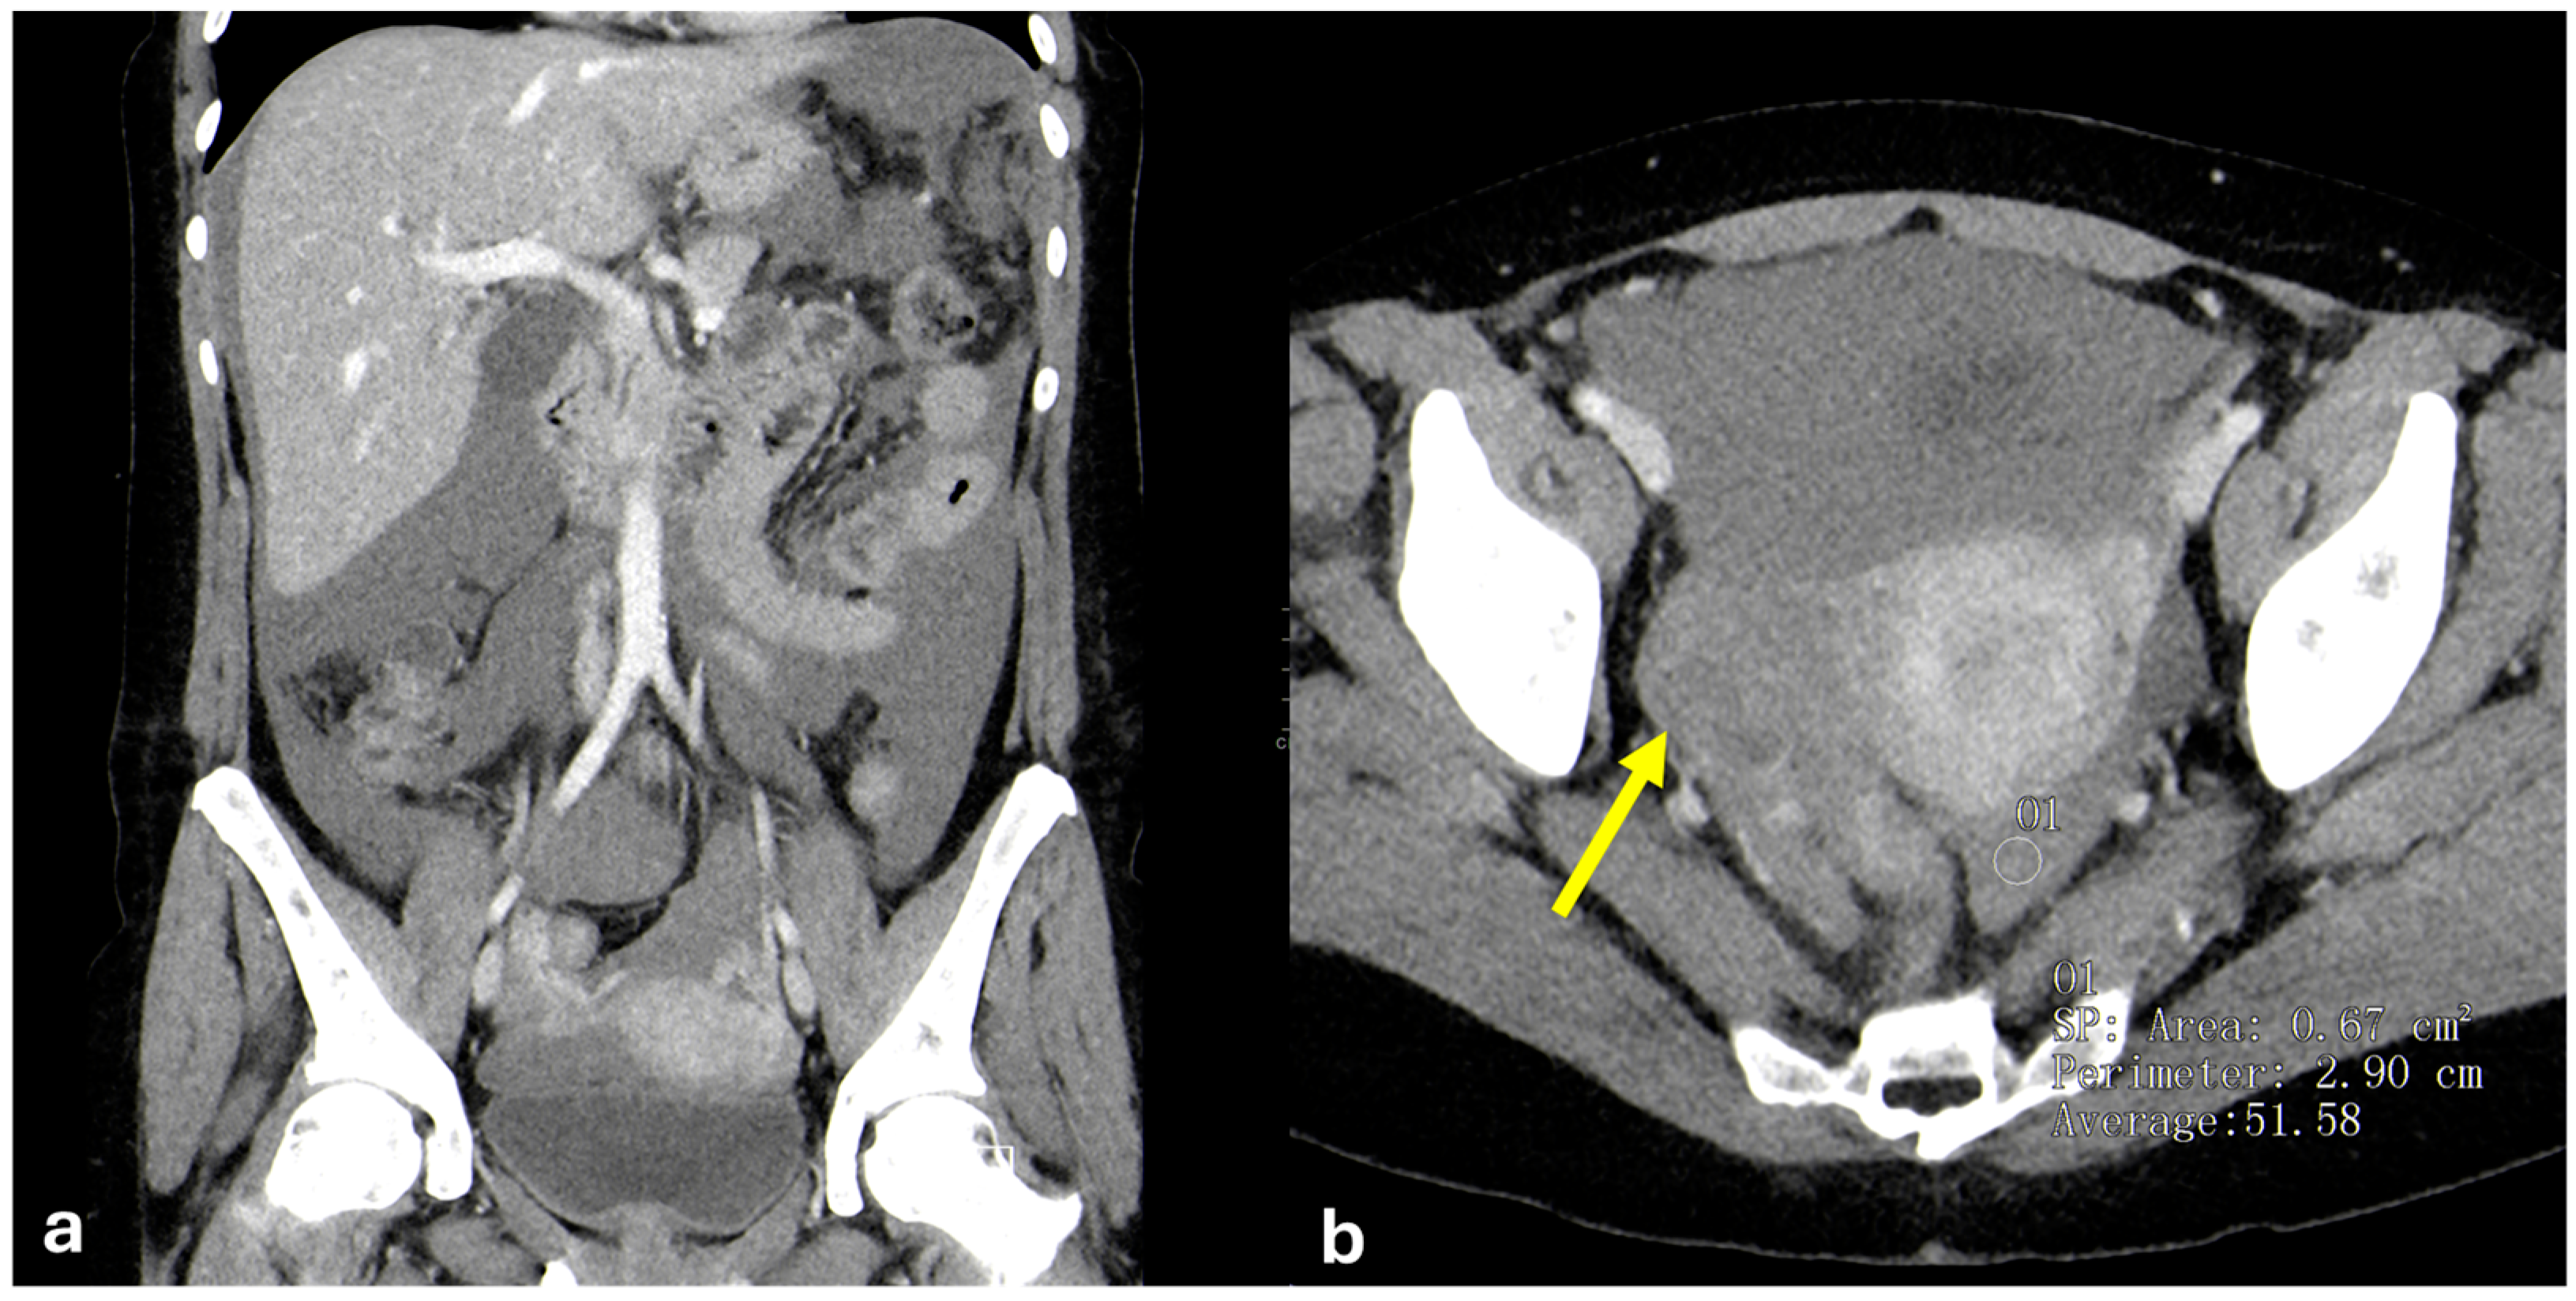

- Micro-nodular pattern: micro-nodules with a diameter ≤ 5 mm (Figure 1);

- Nodular pattern: nodules with a diameter > 5 mm (Figure 2a);

- “Omental cake”: nodular thickening of the omentum (Figure 2b);